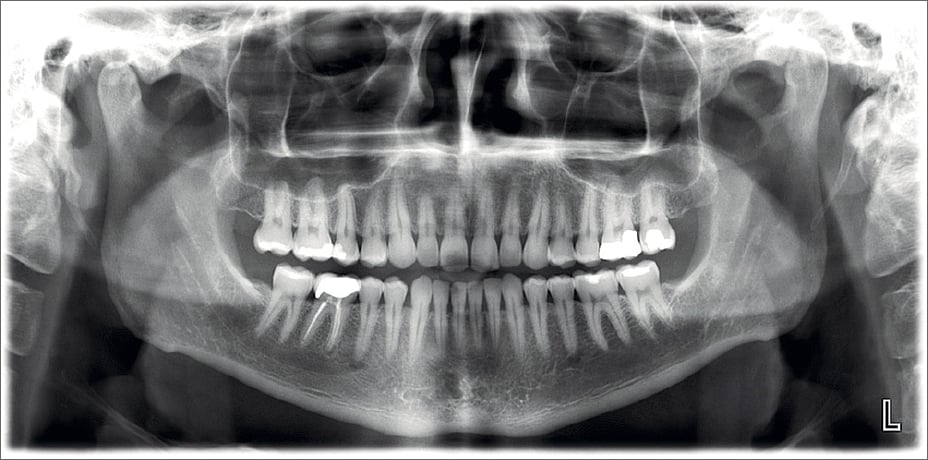

Панорамный снимок зубов (ортопантомограмма) — позволяет увидеть сразу все зубы и челюсти на одном изображении.

Все процедуры проводятся на аппарате Planmeca 3D, обеспечивающем высокую чёткость при минимальной дозе облучения.

Современное оборудование — точность изображения до 0,1 мм, низкое излучение.